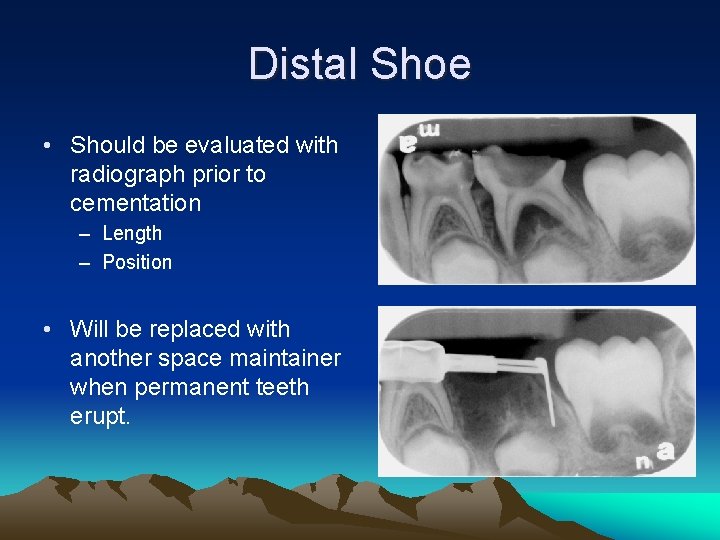

Distal Shoe • Should be evaluated with radiograph prior to cementation – Length – Position • Will be replaced with another space maintainer when permanent teeth erupt.